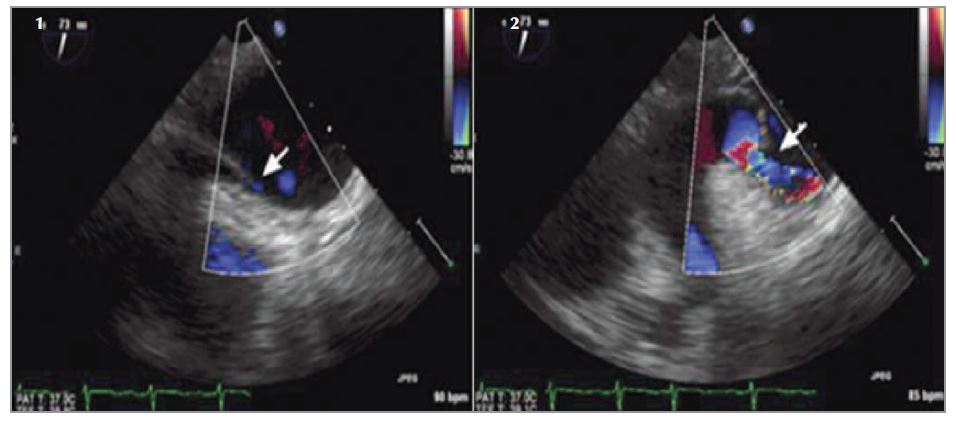

Наличие ШПЛ подтверждается с помощью трансторакальной контрастной эхокардиографии (ЭхоКГ). Раннее появление контраста (в течение 3 сердечных сокращений) в левых отделах сердца свидетельствует о наличии внутрикардиального шунта, в то время как при более позднем появлении (после 6 сокращений) можно думать об экстракардиальном шунтировании [10, 11]. Данный метод используется также в качестве скрининга у больных с наличием гипоксии при различных легочных заболеваниях с целью выявления и локализации анатомических ШПЛ [12–14]. Кроме того, метод позволяет визуализировать внутрилегочные сосудистые мальформации, которые не всегда удается выявить даже с помощью ангиопульмонографии [3]. Трансэзофагеальная ЭхоКГ позволяет более точно анатомически оценить состояние предсердия и межпредсердной перегородки, например наличие незаращенного овального окна (НОО), аневризмы межпредсердной перегородки (АМПП), персистирующего евстахиева клапана – ЕК [15, 16] (см. рис. 1 на цветной вклейке).

Рис. 1 Трансэзофагеальная ЭхоКГ показывает существенную позиционную зависимость внутрисердечного шунтирования: 1 – пациент находится в положении лежа на спине, стрелка указывает на открытое овальное отверстие, через которое не на- блюдается значительного шунтирования; 2 – пациент сидит под углом 90°, через несколько секунд после перехода в вертикальное положение стрелка показывает заметное изменение геометрии перегородки и шунтирование справа налево [31].